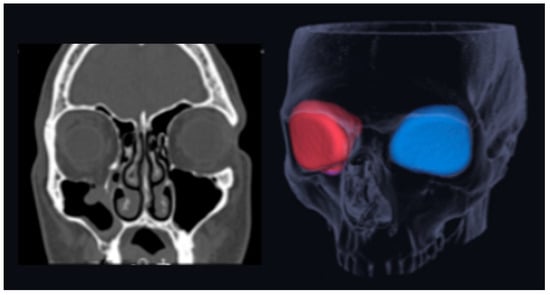

- Chepurnyi, Y.; Chernohorskyi, D.; Prykhodko, D.; Poutala, A.; Kopchak, A. Reliability of orbital volume measurements based on computed tomography segmentation: Validation of different algorithms in orbital trauma patients. J. Craniomaxillofac. Surg. 2020, 48, 574–581. [Google Scholar] [CrossRef] [PubMed]

- Sentucq, C.; Schlund, M.; Bouet, B.; Garms, M.; Ferri, J.; Jacques, T.; Nicot, R. Overview of tools for the measurement of the orbital volume and their applications to orbital surgery. J. Plast. Reconstr. Aesthetic Surg. 2021, 74, 581–591. [Google Scholar] [CrossRef] [PubMed]

- Hahn, H.M.; Jung, Y.K.; Lee, I.J.; Lim, H. Revisiting bilateral bony orbital volumes comparison using 3D reconstruction in Korean adults: A reference study for orbital wall reconstruction, 3D printing, and navigation by mirroring. BMC Surg. 2023, 23, 351. [Google Scholar] [CrossRef] [PubMed]